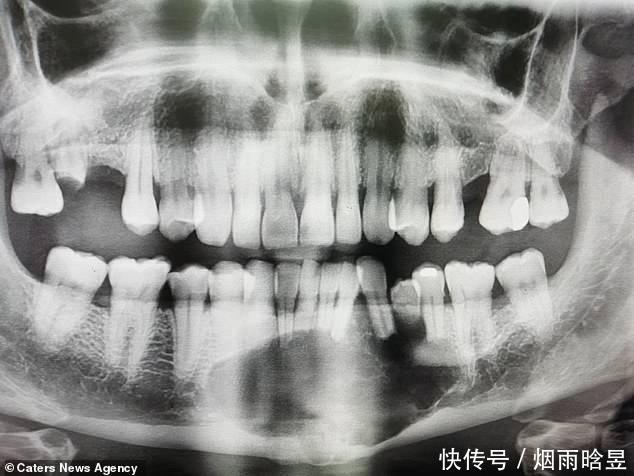

根据X光扫描显示,威尔金森的下颚中间有一个黑洞。随后,他被送到了谢菲尔德的查尔斯克利福德牙科医院,做了两次活组织检查。结果证实这个阴影是一个“巨大的、局部具有侵略性的肿瘤”。

威尔金森被查出患有罕见的成釉细胞瘤,所幸肿瘤并未癌变,该病可能由口腔或下巴受伤、牙齿或牙龈感染或不健康的饮食引起。然而,科学家们还没有完全弄清楚具体的病因。

威尔金森53岁的妻子梅尔说:“通过x光检查,我们得知他患上肿瘤,没想到竟有拳头那么大。他不能吃任何固体的东西,因为他下巴那里有些地方太薄了,吃东西可能会造成骨折。这种病非常罕见,患病几率是500万分之一。我们感觉就像和一颗定时炸弹生活在一起。”